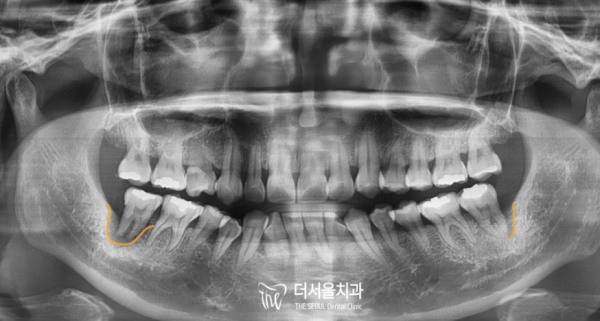

뼈에 잘 심어진 픽스쳐가 결합되는 시간을 거쳐

지르코니아 크라운으로 완성한 모습입니다.

한쪽 임플란트가 완성이 되고, 익숙해지고 나면 반대편도

디지털임플란트로 태평역 더서울치과에서 치료를 하기로 했습니다.

Through the time when the well-planted features are combined,

It's complete with zirconia crown.

When one implant is complete and you get used to it, the other side...

I decided to treat it at The Seoul Dental Clinic at Taepyeong Station with digital implants.